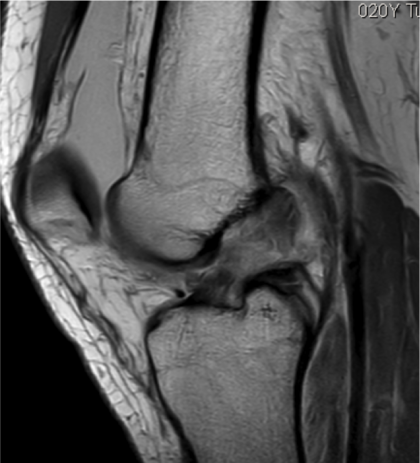

Si bien el diagnóstico puede realizarse con el examen físico (las maniobras semiológicas mencionadas). Los métodos por imágenes son imprescindibles para su confirmación y evaluación del resto de las estructuras (meniscos, hueso). Es importante realizarlos en un lugar confiable y donde los médicos radiólogos tengan comunicación con los traumatólogos. La resonancia magnética es el estudio de elección.

Para una mejor visualización, la resonancia magnética debe realizarse en un equipo de alto campo (1.5 tesla o 3 tesla) que permiten ver lesiones óseas en meniscos u otros ligamentos en profundidad. En cambio, la tomografía computada, sirve para visualizar lesiones asociadas del hueso, con una limitada visualización de partes blandas. En tanto, con una ecografía no se logra visualizar los ligamentos cruzados, ya que son estructuras profundas.